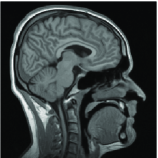

The object of this work is to design an adequate regularization for the problem of recovering missing Fourier coefficients, particularly in some non standard situations were low frequency coefficients are lost. In the framework of non-local regularization, we propose a technique to build an original patchwise similarity measure that is adapted to the missing spectrum. Then, a simple Non-Local quadratic energy is minimized. By construction, the similarity criterion is invariant under the corruption process so that the distance between two patches of the corrupted image is almost exactly equal to the one computed on the clean image. We illustrate our method with experiments which show its efficiency, both in terms of speed and quality of the results, with respect to other common approaches. We show that the method is practical on synthetic examples which are built upon models of inverse scattering problems, synthetic aperture mirrors for spatial imaging or also medical imaging.

The tomography problem for medical imaging or seismic imaging. In this case Fourier coefficients usually lie on straight lines that are either parallel or that cross at the origin.

This procedure is really cumbersome and does not always improve results over the atom-based method. The weight recomputation is not possible for the atom-based distance we introduced since the distance computed on the restored image is exactly the same as the one computed on the corrupted image. However, our method can be used as an initialization for the classical weight recomputation to improve results further. This is the strategy we adopt in the following tomography problem where the Fourier coefficients got corrupted by a Gaussian noise of magnitude :

| Original | Spectrum of | Corrupted | Spectrum of |

![]() |

| PSNR=22.4dB |